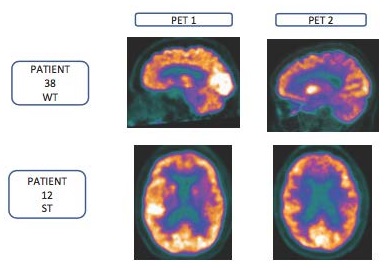

Scansioni PET di due pazienti, senza (riga sopra) e con intervento nutrizionale (riga sotto) con la bevanda contenente Fortasyn Connect® all'inizio e dopo otto mesi di intervento.Un nuovo studio longitudinale ha dimostrato che una bevanda nutrizionale definita 'alimento per scopi medici speciali' contenente la combinazione multinutriente Fortasyn Connect® può giovare ai pazienti con lieve deterioramento cognitivo, la fase che precede il morbo di Alzheimer (MA), che rischiano di progredire verso la demenza di MA.

Alla visita di inclusione sono stati condotti test neuropsicologici e scansioni PET con 18F-FDG, e dopo un anno c'è stato un nuovo controllo, che comprendeva anche un esame neurologico e una Subjective Changing Scale (scala di cambiamento soggettivo) completata dal caregiver. Diciassette pazienti hanno ricevuto il prodotto mentre 24 pazienti erano nel gruppo senza intervento e due pazienti si sono ritirati.

Gli studi di scansione F-FDG-PET forniscono una misura del numero di sinapsi in una regione del cervello (questo numero diminuisce nel lieve deterioramento cognitivo quando progredisce verso il MA più avanzato); è stata valutata la capacità di questo alimento per scopi medici speciali di influire su questa diminuzione del numero di sinapsi.

Le scansioni PET 18F-FDG hanno mostrato un significativo peggioramento del gruppo senza intervento nutrizionale rispetto al gruppo che riceve il prodotto. Nel gruppo senza intervento c'è stato un significativo peggioramento delle prestazioni della memoria, delle funzioni esecutive e dell'attenzione, mentre il gruppo che ha ricevuto il prodotto ha mostrato una stabilizzazione in queste misure di esito.

"Invece di bloccare l'effetto di una neurotossina, i dati suggeriscono che, fornendo supporto nutrizionale, può aiutare i neuroni del cervello a creare più sinapsi. Questa ipotesi è supportata dai nuovi dati sul PET 18F-FDG secondo i quali c'è stato sia un significativo peggioramento negli individui che non avevano ricevuto l'intervento nutrizionale, sia un peggioramento minore tra quelli che ricevevano l'intervento. Cioè, come si suol dire, un «gran risultato»".